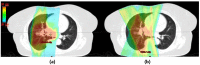

Radiation therapy is a major treatment modality for management of non-small cell lung cancer. Radiation pneumonitis is a dose limiting toxicity of radiotherapy, affecting its therapeutic ratio. This review presents patient and treatment related factors associated with the development of radiation pneumonitis. Research focusing on reducing the incidence of radiation pneumonitis by using information about lung ventilation, imaging-based biomarkers as well as normal tissue complication models is discussed. Recent advances in our understanding of molecular mechanisms underlying lung injury has led to the development of several targeted interventions, which are also explored in this review.